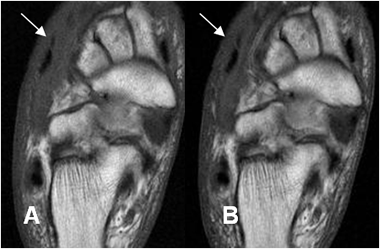

Fig 124 A. Pie diabético. Celulitis.

A: RM coronal en T1 y B: RM coronal en STIR. Edema de tejidos blandos en el dorso del pie, por celulitis. No hay compromiso óseo.